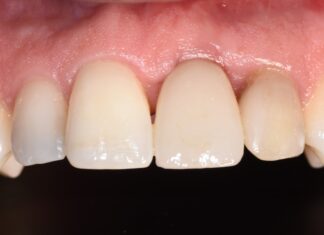

Mantenimento del profilo tissutale nell’impianto post-estrattivo ritardato: obiettivo realistico?

Gestione chirurgico-protesica di un sito implantare post-estrattivo, con focus sulla gestione del profilo tissutale nell’impianto post-estrattivo mediante il restauro provvisorio, utilizzato come supporto per...